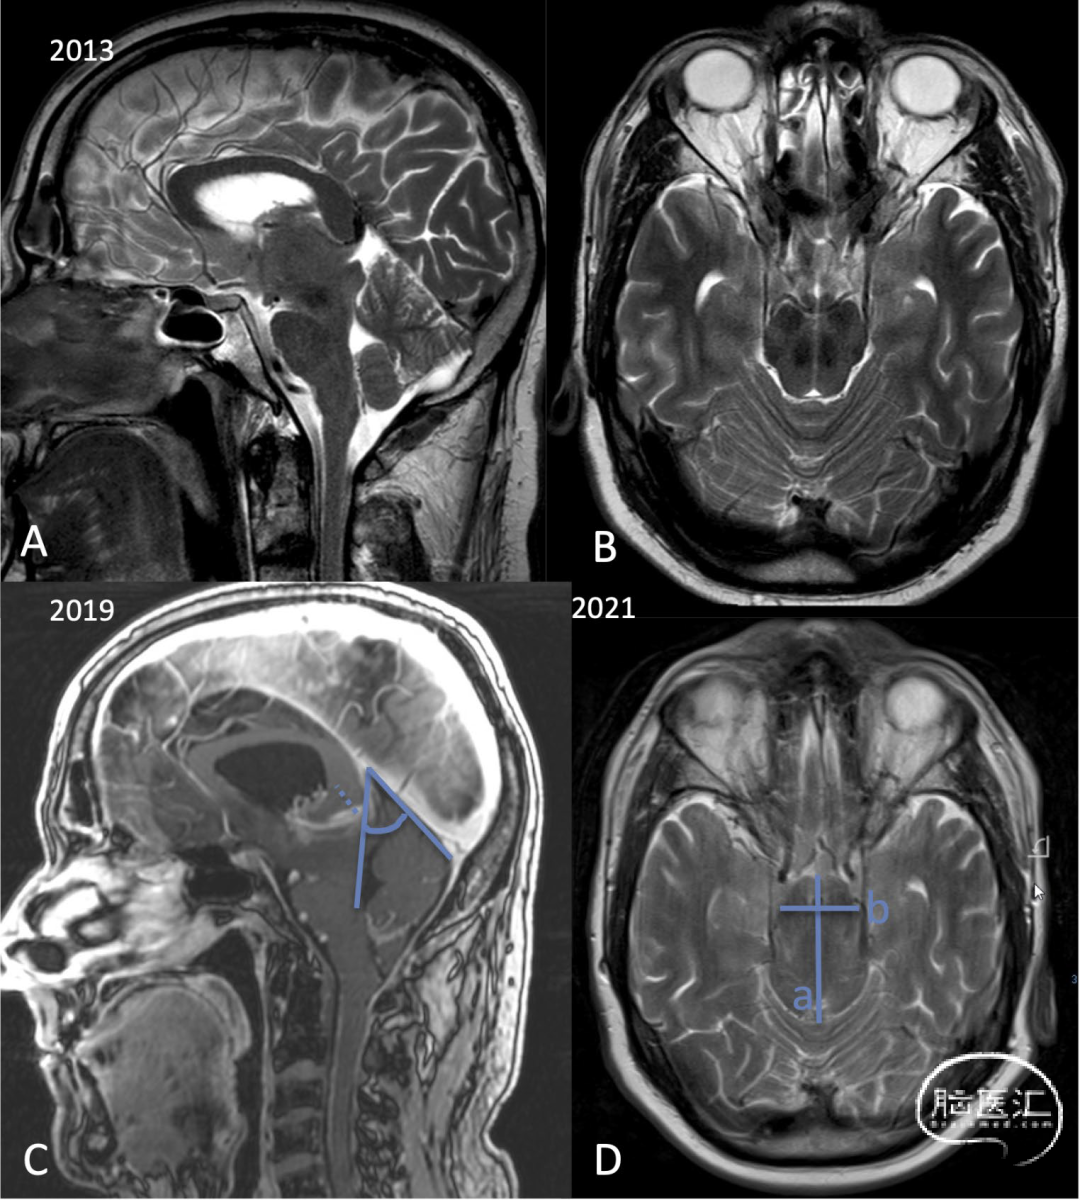

图1.男性,57岁。表现为冷漠、缺少兴趣、步态共济失调和震颤。在至少6年的时间里,症状恶化,以至于整天都坐在家里看电视。矢状位(A)T2加权和增强MPRAGE图像(C)显示Galen静脉和直窦之间有一个小角度(C:角度)。Galen静脉延长(从大脑内静脉汇合处到Galen静脉在直窦出口的距离)(C:虚线箭头)。轴位T2加权图像(B、D)显示,中脑变长: